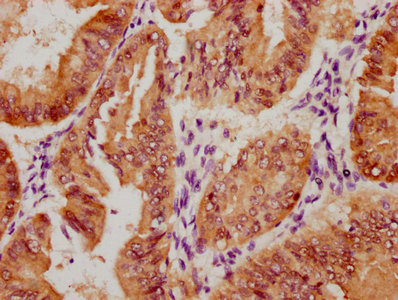

Immunohistochemical analysis of paraffin-embedded Human-colon, antibody was diluted at 1:100

Immunohistochemical analysis of paraffin-embedded Human-colon, antibody was diluted at 1:100